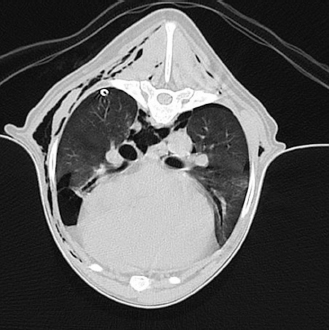

A 12-year-old male neutered Shih Tzu with a body weight of 6 kg was presented to the emergency service of the Small Animal Clinic of the Freie Universität of Berlin due to acute onset of respiratory distress without any history of trauma or preceding respiratory symptoms. At presentation, the dog showed mild dyspnea with a respiratory rate of 40 breaths per minute with increased abdominal effort but reduced thoracic motion. Auscultation of the thorax revealed damped respiratory sounds on both sides without alteration in heart sounds indicating a pneumothorax. All other parameters of the general examination were within normal range. Bilateral thoracocentesis was performed until dyspnea had significantly improved, evacuating 250 ml air in total dyspnea resolved after initial thoracocentesis, and a dorso-ventral thoracic radiograph was taken. Subsequent radiography of the chest in the dorso-ventral projection showed marked retraction and increased radiopacity of the right and left lung lobes, confirming severe bilateral pneumothorax and the tentative diagnosis of spontaneous bilateral pneumothorax was made (Fig. 2). No radiographic signs of bullae or other pathologic conditions such as lung tissue masses could be detected on the dorso-ventral view. Further radiographic imaging was suspended to reduce the patient’s stress level and to prevent possible recurrence of dyspnea. Besides mild thrombocytosis (742 103/µl; range 165–400), no abnormalities were found on complete blood count and blood chemistry analysis.

Fig. 2. Radiographic image of the thorax in dorso-ventral view with the dog in sternal recumbency after thoracocentesis for initial patient stabilization. Severely collapsed lung lobes with retracted lung lobe margins are visible on both sides.